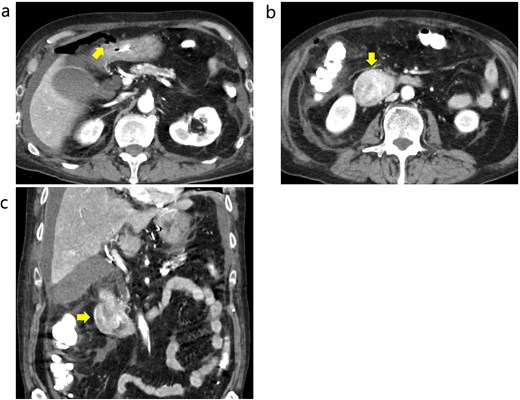

A 70-year-old male who worked as a farmer following retirement from office-work was referred to our hospital with anorexia, nausea, and abdominal pain. The patient had a history of hypertension, diabetes mellitus, gastroesophageal reflux disease, and benign prostatic hyperplasia. He had not smoked for 10 years and consumed one glass of the alcoholic beverage shochu daily. Contrast-enhanced computed tomography (CT) of the abdomen revealed peritonitis/duodenal perforation and a 4 cm duodenal tumor in the 1st and 2nd duodenum portions, respectively (Fig. 1a–c). Emergency laparotomy was performed to close the perforation. Gastroduodenal endoscopy revealed duodenal stenosis with a tumor in the 2nd portion (Fig. 2). Biopsy indicated a poorly differentiated adenocarcinoma; however, magnetic resonance imaging (MRI) showed no stenosis in the bile or pancreatic ducts (Fig. 3a and b). Preoperative laboratory data revealed normal levels of the tumor markers carcinoembryonic antigen (CEA) 1.5 (<5.0) and CA19–9 12.6 (<37.0).

Contrast-enhanced CT before emergency surgery. (a) Free air was observed around the anterior wall in the duodenal bulb, and a perforation in the 1st portion was notes. The arrow indicates free air. (b and c) The tumor in the 2nd portion of duodenum was well enhanced. The arrows indicate the tumor.